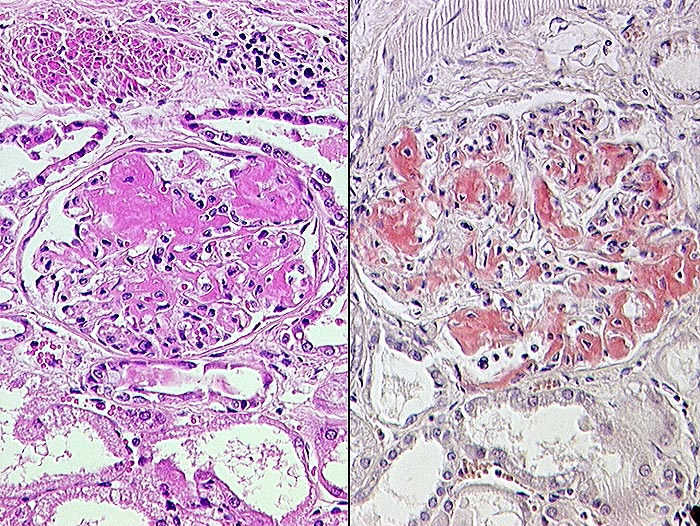

Rechts: Kongorote Amyloidablagerungen in den Glomeruli.

Links: HE-Färbung.